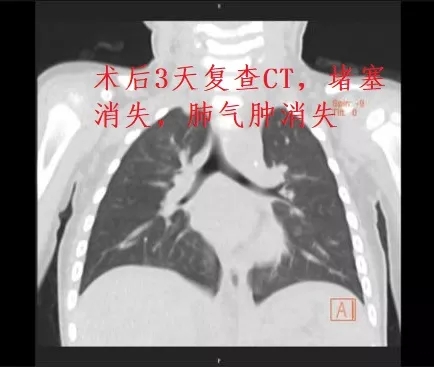

完善术前准备后,医护人员立即送患儿至内镜中心行手术治疗。手术由韦庆主任携科室团队进行,全麻下支气管镜顺利通过口咽部进入主支气管,到达隆突气管分叉处,镜下可见异物已将右主支气管开口处完全堵住,手术历时一小时余,最终将异物分解再通过冷冻探头分次取出,镜下同时见到气管内有较多脓性分泌物,考虑异物堵塞刺激发炎所致。术后继续抗炎治疗,3天后复查胸部CT,可见气道通畅,肺气肿已消失。

术后CT检查